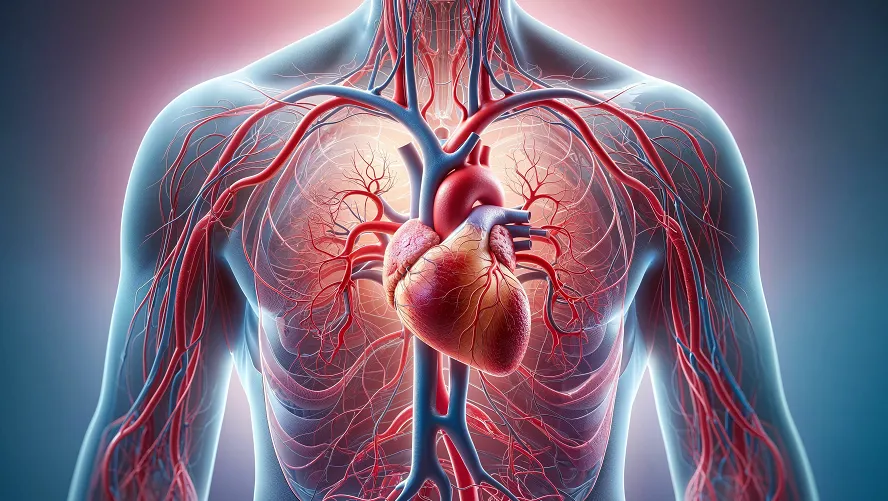

As we age, maintaining healthy blood flow becomes increasingly crucial—and challenging. Poor circulation in seniors isn’t just about cold hands and feet; it can lead to fatigue, slower healing, cognitive fog, and increased risk of heart disease, strokes, or peripheral artery disease (PAD). The good news? Significant improvements are possible with targeted, safe strategies. Here’s your evidence-based guide to boosting circulation and enhancing quality of life for elderly individuals.

Aging causes significant changes that impair blood flow. Arteries stiffen (arteriosclerosis) due to elastin loss and collagen buildup, reducing flexibility and increasing blood pressure. Fatty plaque (atherosclerosis) narrows vessel pathways, restricting flow. The heart muscle thickens slightly, reducing its pumping efficiency and cardiac output, especially under stress. Blood vessels produce less nitric oxide, limiting their ability to widen (endothelial dysfunction). Reduced total body water often lowers blood volume, and capillary walls thicken, slowing oxygen/nutrient exchange. These cumulative changes hinder circulation, particularly to extremities and vital organs.